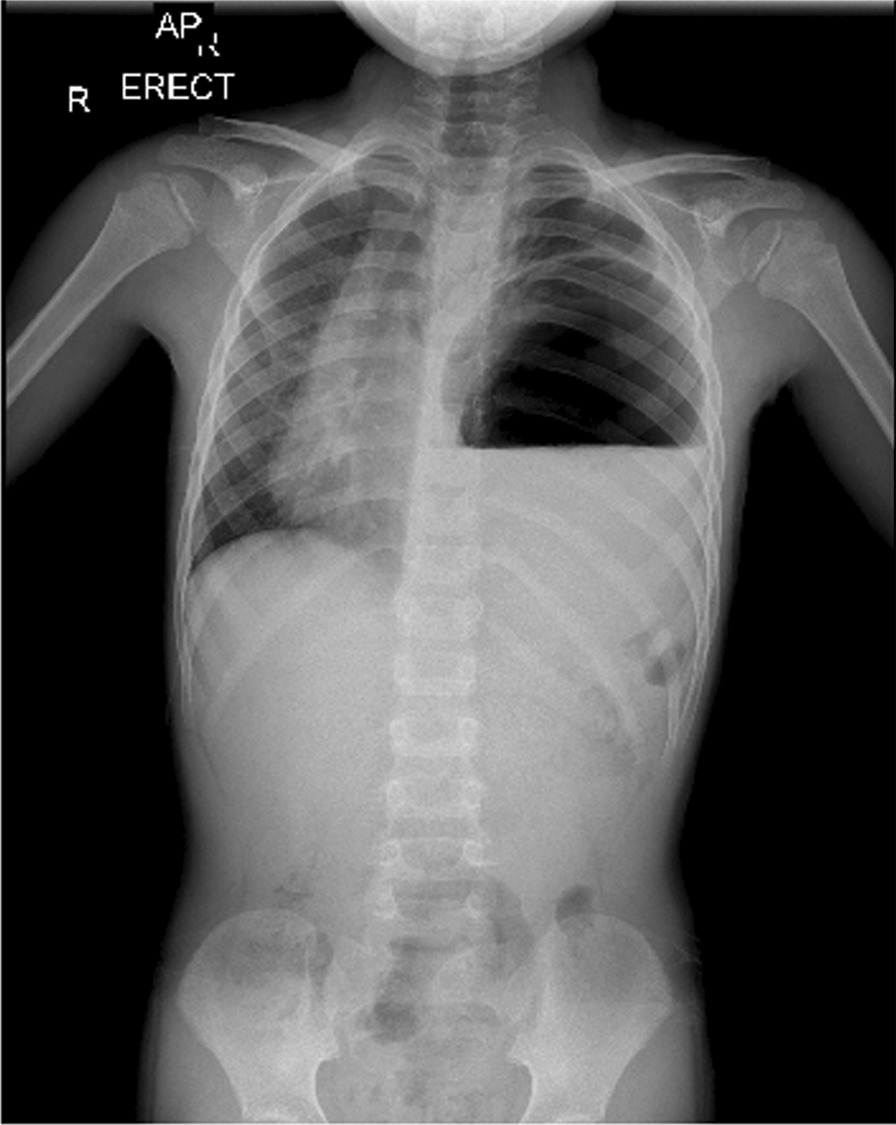

The patient’s blood pressure (BP) was 135/75 mmHg, pulse rate (PR) was 75 beats per minute, temperature was 36.7 °C, respiratory rate (RR) was 40 breaths per minute, and blood oxygen saturation (SpO2) was 99%. On examination, there was a marked decrease in lung sounds on the left side, while auscultation on the right lung was normal. The heart sound was typical and louder on the right side. His abdomen was soft and nontender with no palpable masses, and the rest of the systemic examinations were normal. CXR and initial laboratory blood tests were requested. On CXR, a round-shaped lesion with relatively clear boundaries containing air–fluid level, as well as shift of the heart and mediastinum to the right, was seen (Fig. 2). Hydatid cyst and lung abscess were among our early differential diagnosis based on the CXR. The patient was admitted to the pediatric intensive care unit (PICU) immediately because of mild tachypnea and hypotension. The patient was nil per os (NPO) and received oxygen through a nasal cannula; he was continuously monitored by pulse oximetry and cardiac-monitoring device. Intravenous hydration, clindamycin, ceftriaxone, and vancomycin were administered.

Fig. 2.

CXR showing a round-shaped lesion with relatively clear boundaries containing air–fluid level, as well as shift of the heart and mediastinum to the right